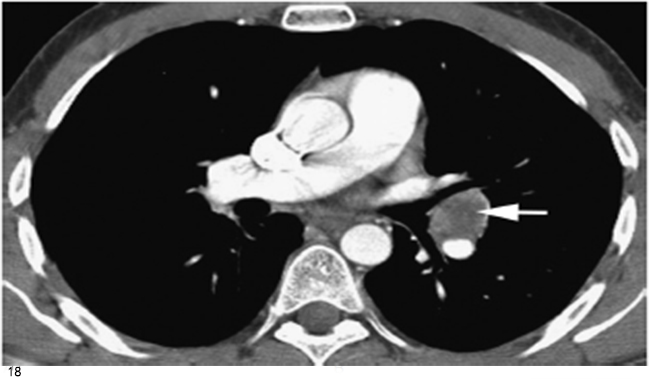

五、肺门肿块或淋巴结增大

影像学上肺门增大提示起源于中央区域的原发性肿瘤(模糊肺门肿块)(图17) 或周围型肺癌肺门淋巴结转移(边界清楚肺门肿块)(图18)。鳞癌常见。肺门淋巴结增大与中央肿块融合是小细胞肺癌的特征(图13)。

图18 周围型肺癌转移伴左肺门淋巴结增大(箭头)

肺门肿块边缘锐利